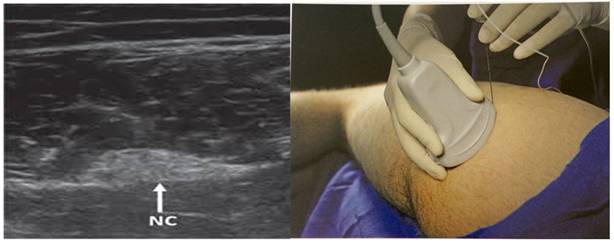

Por último se colocó al paciente en decúbito lateral y se procedió a bloquear el nervio ciático a nivel glúteo, ecoguiado con sonda recta de alta frecuencia y aguja ecorrefringente de 100 mm (Pajunk®), se administró 15 ml de bupivacaína 0,5 % sin adrenalina.

Para ello luego de identificar el trocánter mayor y la tuberosidad isquiática, colocamos la sonda en el punto medio de una línea imaginaria entre estos, identificaremos las distintas estructuras: musculo glúteo mayor y cuadrado femoral. El nervio ciático suele estar colocado profundo a la fascia del glúteo mayor, más cerca de la tuberosidad isquiática, generalmente con forma aplanada o elíptica (figura 6).

Figura 6 A izquierda, se muestra la imagen ecográfica del Nervio Ciático (NC). A derecha, la posición de la sonda ecográfica para obtener la imágen